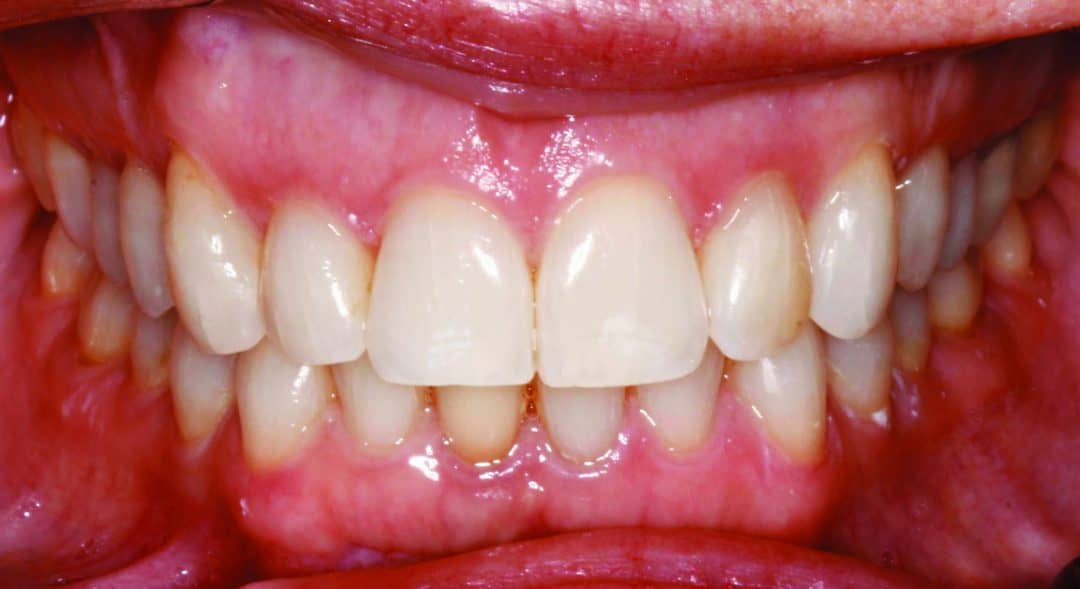

Actual before and after of Invisalign treatment needing refinement Aligner Refinement It is not a bad thing if your dentist suggests refinements, it just means that they are making sure you get the most out of your treatment. When the teeth are not being aligned properly, or the gaps between the teeth are not being closed as planned, it may be necessary to make adjustments. Invisalign refinements are additional sets of. Aligner Refinement.